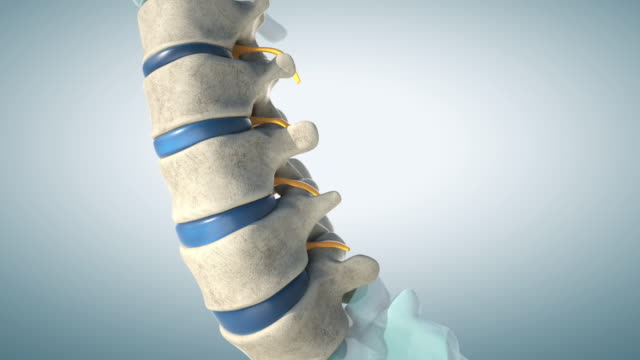

1. 척추 분리 성 척추 전방 전위증

어릴 때부터 척추뼈가 분리되어 척추가 앞뒤로 움직이는 상태입니다. 이러한 상태는 척추의 안정성을 감소시키고 전방 전위를 유발합니다.

2. 퇴행성 변성으로 인한 척추 전방 전위증

나이가 들면서 40대, 50대, 60대가 되면 척추는 퇴행적인 변화를 겪게 됩니다. 이로 인해 척추뼈가 변성되고 미끄러지게 되며, 이러한 변화가 전방 전위를 초래합니다.